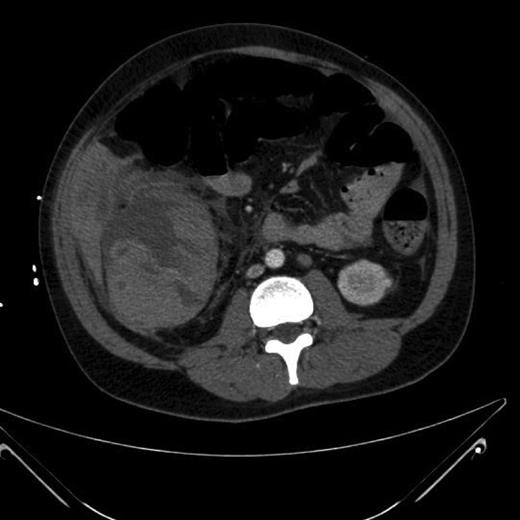

Since his history and clinical findings were very suspicious of TB, he was reviewed by the respiratory team. Empirical anti-tubercular therapy was suggested after sputum cultures were sent for acid fast bacilli (AFB) and a CT thorax showed a right upper lobe collapse and a 3-cm apicoposterior cavity. There was also consolidation seen in the right middle and lower zone as well as the left lung (Fig. 1). Also noted was right-sided neck lymphadenopathy (largest 17 mm). All these findings were consistent with pulmonary TB.

CT thorax—right-sided upper and mid zone collapse + consolidation.